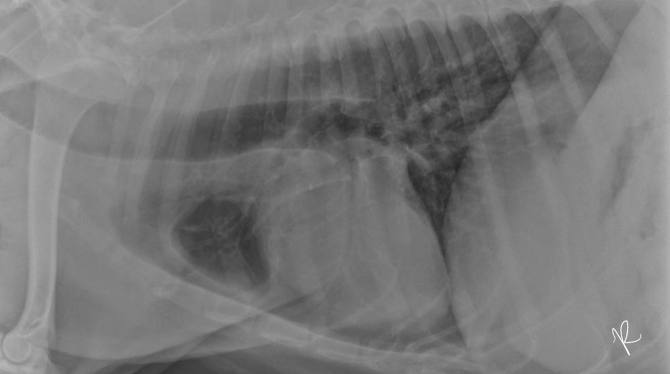

14

Juvenile idiopathic megaesophagus